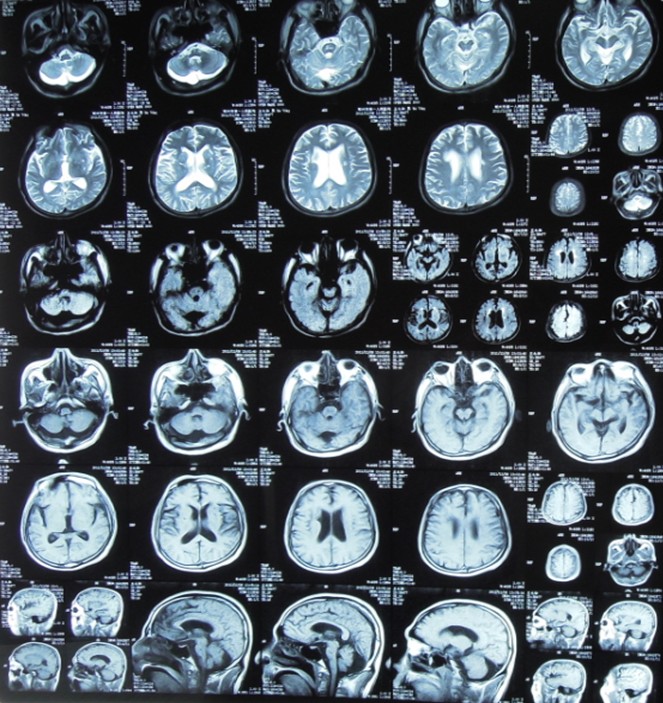

头MRI始终未发现新病灶。

存在问题:确实存在脑血管病(确切的血管狭窄);神经系统症状自入院后逐渐加重(8-10天达高峰);头MRI始终未发现新责任病灶。